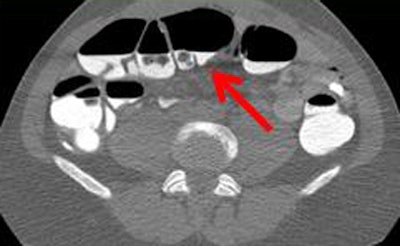

| Poor quality (1, above) means there is significant stool that is incompletely tagged; average (2, below) denotes that some incompletely tagged stool is present; and medium (3, bottom image) represents good overall quality with some stool that is not completely tagged. Superior quality (4) is generally not obtained in reduced-prep regimens. |

The qualitative analysis demonstrated that the "medium image quality was in the group that used a major amount of DD beginning the day before the VC scans, because there is time for the DD to mix with water and feces in the colon," Ferrari said.